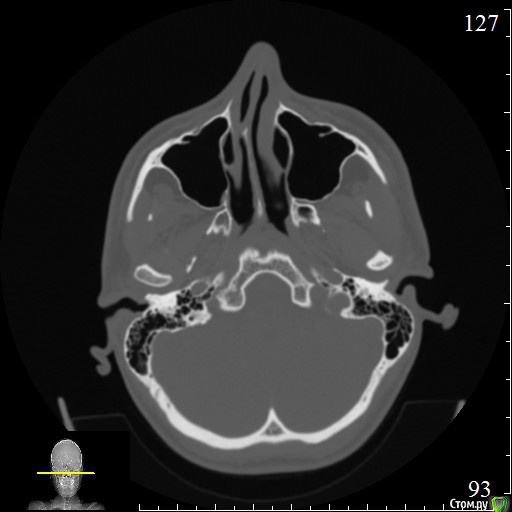

Dmitriytd Опубликовано 19 августа, 2020 Поделиться Опубликовано 19 августа, 2020 Здравствуйте, пожалуйста, посмотрите КТ( сделано в стоматологической клинике). Беспокоят проблемы с носом(постоянные прозрачные выделения, боли в пазухах, особенно при наклоне головы вниз). Знакомый лор посоветовал проверить на одонтогенный гайморит и я вспомнил, что делал КТ два года назад.Ссылка на КТ:https://yadi.sk/d/64pLNRildrWt5A Ссылка на комментарий

Dmitriytd Опубликовано 11 сентября, 2020 Автор Поделиться Опубликовано 11 сентября, 2020 Два года -кт не актуаленЗдравствуйте, сделал новое КТ. Пожалуйста, посмотрите:https://yadi.sk/d/1sbzO9z0QrurZg Ссылка на комментарий

wladdX Опубликовано 11 сентября, 2020 Поделиться Опубликовано 11 сентября, 2020 На мой взгляд, ничего примечательного в верхнечелюстных синусах нет. 1 Ссылка на комментарий